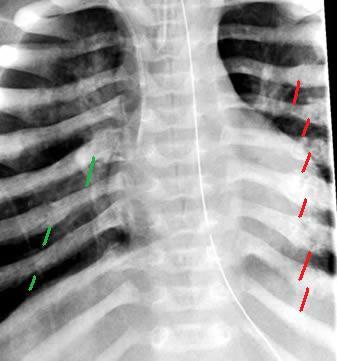

This image shows fractured ribs, circled in red.

Here’s another example of multiple fractured ribs, with the fractures indicated via arrows: